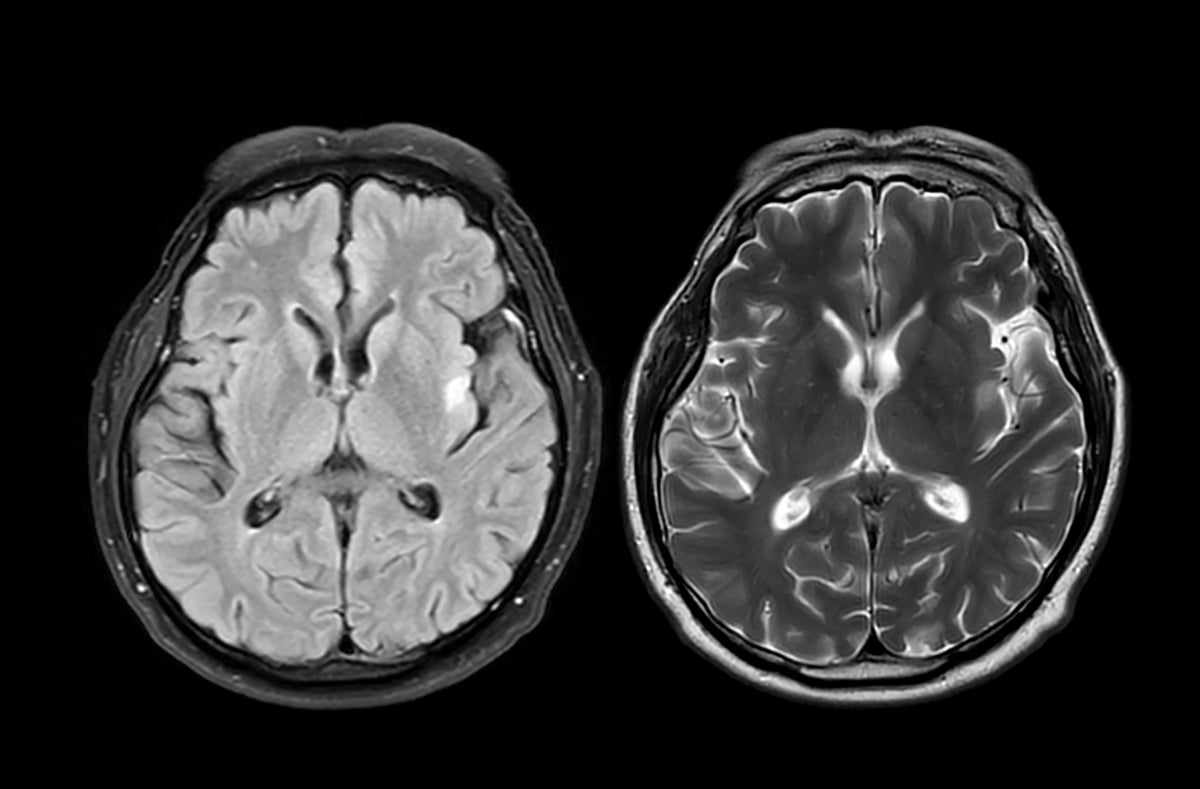

Researchers in the U.K. analyzed brain scans from nearly 1,000 healthy adults before and during the COVID-19 pandemic. What they found was surprising: people living through the pandemic showed signs of accelerated brain aging. Their brains appeared about five and a half months older than expected when compared to prepandemic trends.

So how did they figure this out? The scientists used data from the U.K. Biobank, a massive health database that includes brain imaging from tens of thousands of participants. They trained a machine-learning model to estimate “brain age” based on hundreds of structural features seen in MRI scans. Then they compared two groups: people who had both scans before the pandemic and those who had one scan before and one during the pandemic.